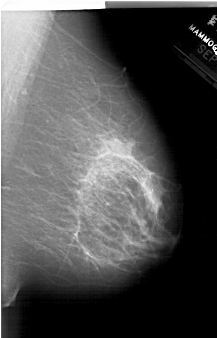

A_1514_1.RIGHT_CC

RIGHT_CC LINES 6466 PIXELS_PER_LINE 4021 BITS_PER_PIXEL 12 RESOLUTION 43.5 NON_OVERLAY